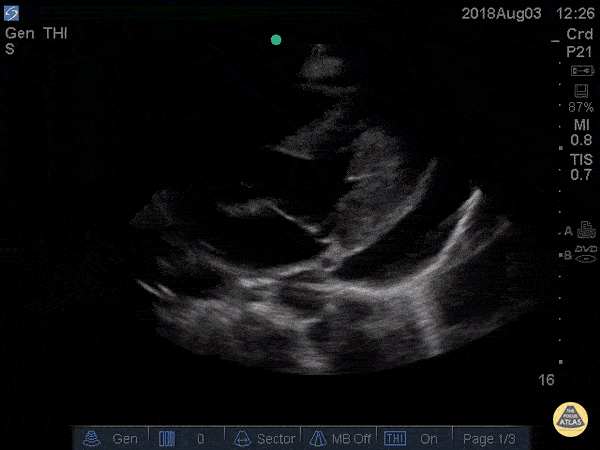

Pericardial Disease - Cardiac Tamponade Parasternal Long

41 yo M with history of stage 4 lung cancer presents with AMS and dyspnea, normotensive and tachycardic to 140s. Parasternal long view showed moderate pericardial effusion with RV collapse. With M mode we are able to see the RV wall collapse (top line) corresponds with the mitral valve opening i.e. it occurs during diastole. Even though the patient was normotensive he was taken to the OR for a pericardial window within the hour given this evidence of echocardiographic tamponade. Nathan Kabariti MS4, Dr. Charles Murchison, Dr. John Riggins, Dr. Donald Doukas - Kings County Emergency Medicine